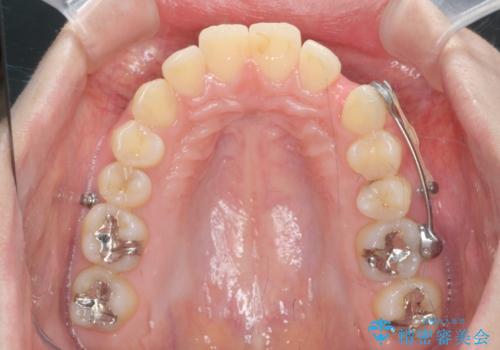

カリエール・マイクロインプラントを用い、時間はかかりましたが大きく歯の後方移動が達成され、前歯の見た目が大きく改善されました。

大きな後方移動を達成するにはマイクロインプラントと日常的なゴムかけが大切です。